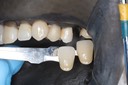

Chris Woo #30 try in

Chris Woo #30 finish